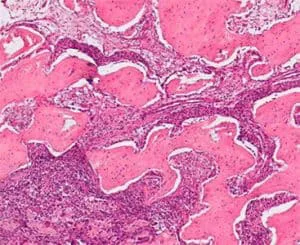

Получив базовое ветеринарное образование, она получила степень магистра (MS) в области ветеринарной анестезиологии (2002), степень доктора наук (PhD) в в области ветеринарной патологии (2009 г.) и закончила резидентуру по ветеринарной анатомической патологии в 2009 г.